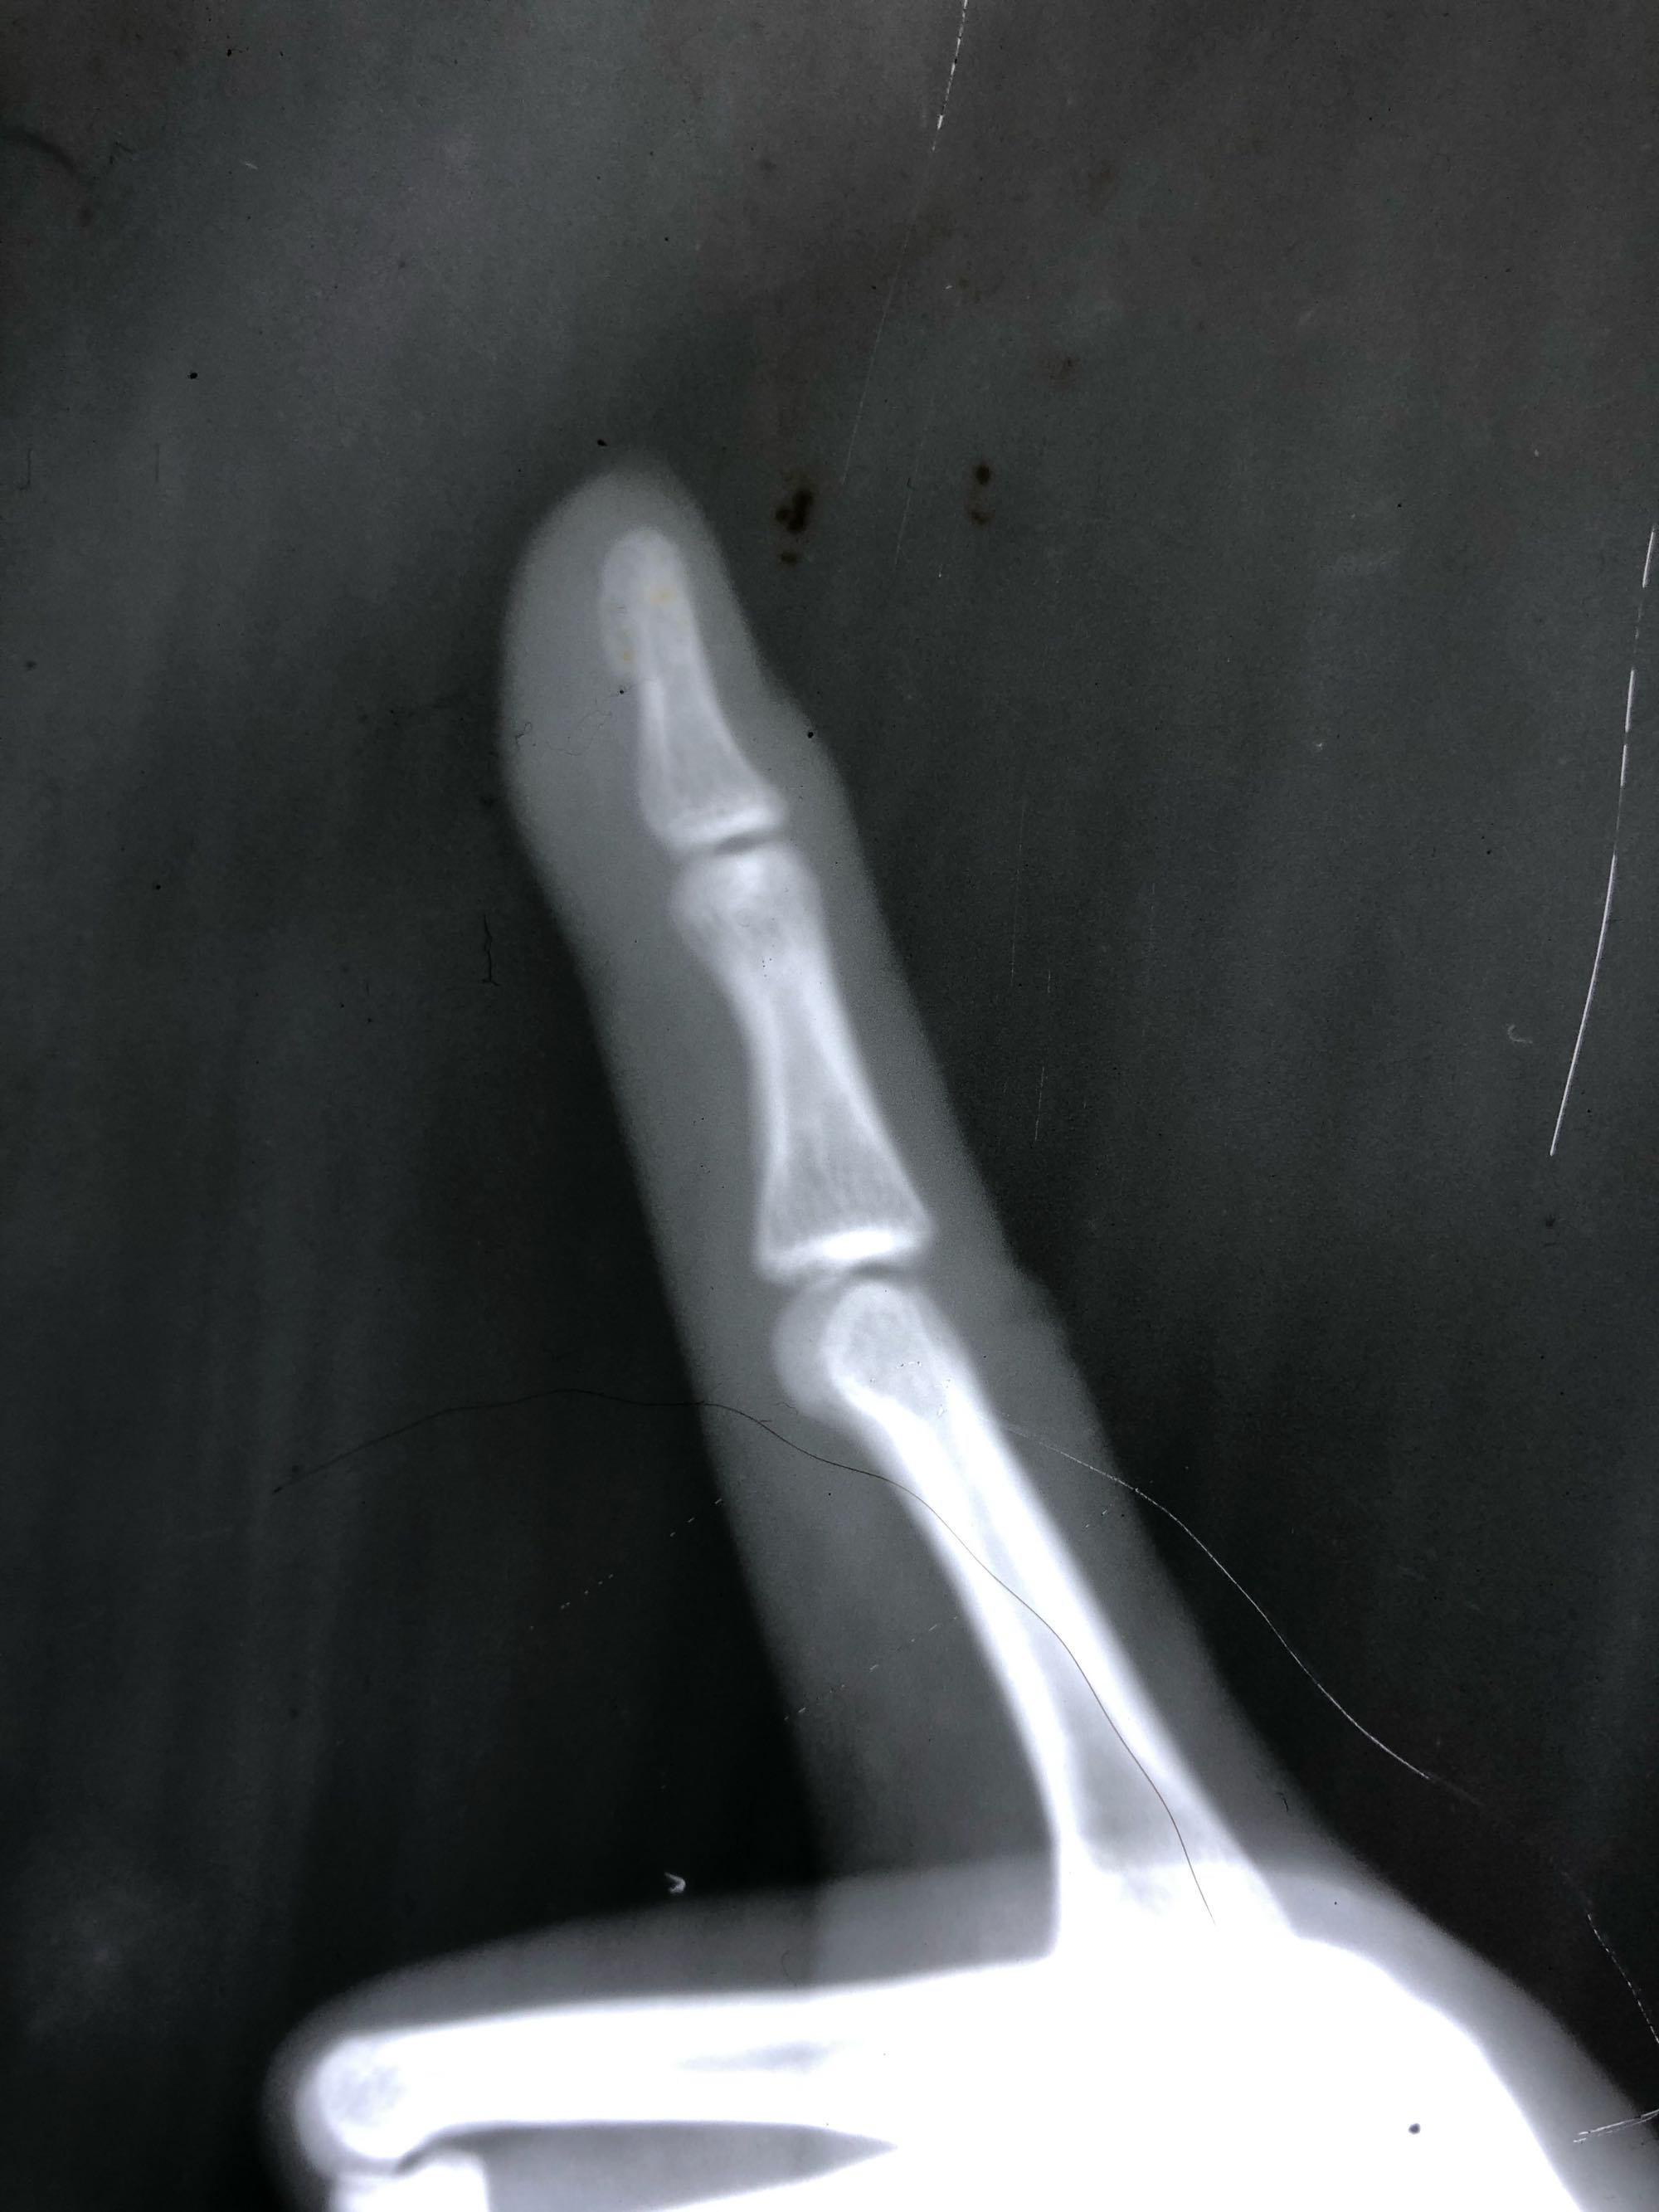

大夫帮我看看这个x光,指尖骨的地方小米粒发小的局部外力压迫就会疼痛,十几年了,今天去看了答复说是脂肪瘤,说不需要手术,手术之后变成硬块还是会疼,你的建议是就这么地还是做手术?

片子看软组织看不出来任何信息